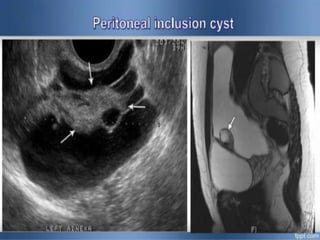

Peritoneal Pseudo cyst (PPCS)

Cysts formed by

trapping and

collection of fluid

inside Post

inflammatory &

Postoperative

adhesive pockets

of peritoneal

cavity.

PPSC (bizarre lump-shaped cyst)

Thin wall

• Fine internal septations .

• ovary suspended among

adhesions.

cogwheel appearance

Note:

nodular mesothelial

tissue projections

(straight arrows)

Normal ovary and

follicles adjacent to

peritoneal inclusion

cyst (curved

arrows).